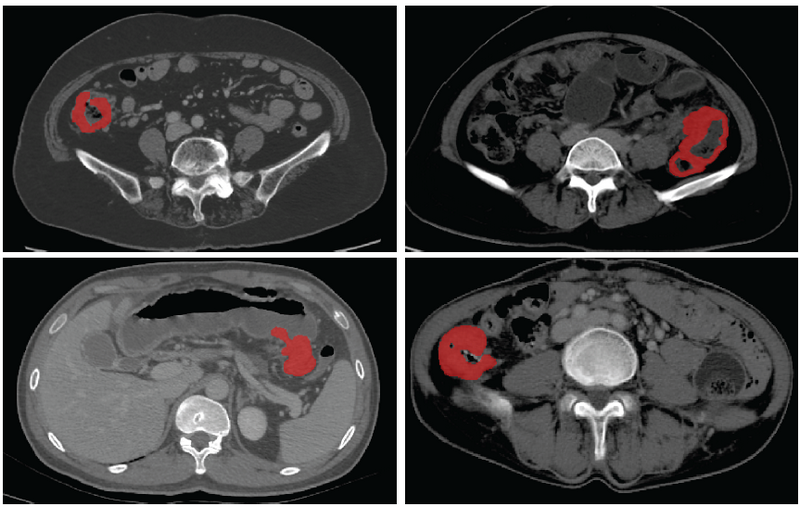

基于CT影像的结肠癌病灶分割

据介绍,基于医学影像的人工智能为肠癌个体化诊疗提供了巨大的可能性,已经有多项研究实现了病人的疗效预测、术后复发风险评估,但这些应用无不依赖于精准的病灶分割。此次SOUSA技术的开发在国际上首次实现了结肠癌的自动分割,为加速肠癌人工智能精准诊疗的临床应用奠定了基础。自动化标准化的精准影像信息处理将有效地降低经济、时间和人力成本,为精准诊疗的实施提供了重要的临床依据,具备极大的临床转化应用前景。

对肠癌数据集使用不同方法的自动分割结果